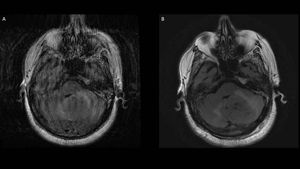

Cartesian 2D T2-w FLAIR (A) and non-Cartesian (PROPELLER) 2D T2-w FLAIR (B)

Cartesian acquisition suffers from severe motion artifacts, while non-Cartesian acquisition easily highlights the cerebellum tumour, offering diagnostic imaging. Images courtesy of Christos Tsiotsios.